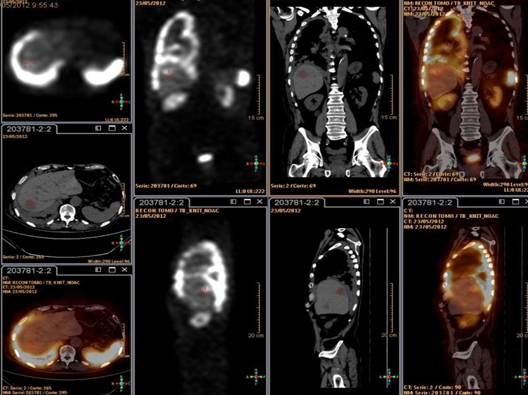

Las vistas tomográficas reconstruidas a partir del SPECT mostraron zonas de captación del trazador en proyección de los órganos antes mencionados. Utilizando los volúmenes de la TC y el SPECT con análogos de la somatostatina y aplicando el software de fusión de imágenes (fig. 3), se obtuvo información anátomo -funcional de las lesiones descritas por separado en la tomografía y en la gammagrafía.